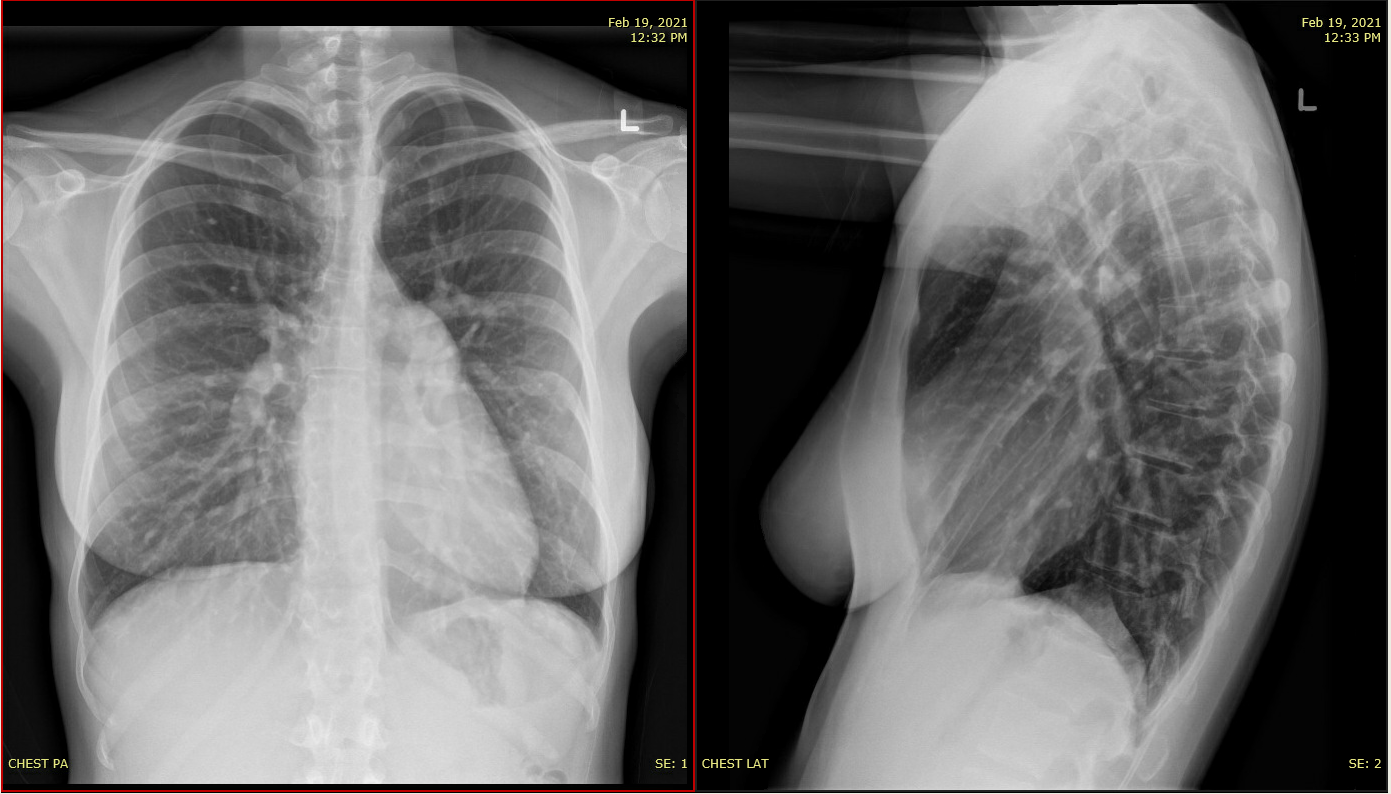

ASD Case

- 29 yo F with lifelong palpitations and new shortness of breath on exertion - specifically with stairs and with vigorous activity

- Physical exam: RV heave, S1, S2 split, soft murmur over left sternal border. No signs of heart failure